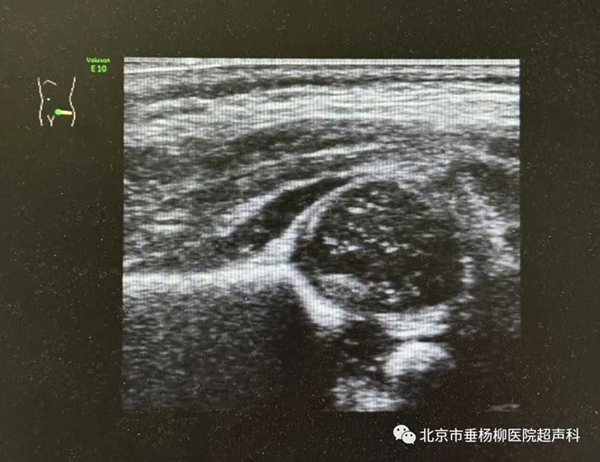

小儿常见病,如肠梗阻、阑尾炎、肠系膜淋巴结炎、肠套叠、Meckel憩室、胆囊炎、泌尿系统结石等可做出快速诊断;同时在幽门肥厚、颅内出血、脑积水、子宫及卵巢的发育监测、髋关节发育不良、感染性病变及肿瘤等方面中有重要诊断价值。